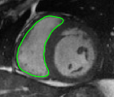

The problem above is a generalization of Horn & Schunck optical flow. Note that solving for the Horn & Schunck optical flow within each region separately does not lead to motions such that at the interface, they have equal normal components (see Figure 1), whereas the solution of (5) to be presented in subsequent sections does. Note that computing Horn & Schunck optical flow in each region requires boundary conditions (and typically they are chosen to be Neumann boundary conditions: and on ). Note that replacing these boundary conditions with the boundary constraint (6) does not specify a unique solution. Also, while Horn & Schunck optical flow computed on the whole domain naturally gives a globally smooth motion, which by default satisfies matching normals at the interface, this is not natural for the ventricles / myocardium, where different motions exist in the regions (see Figure 2), and the motions should not be smoothed across the regions.

![]() |

| image + boundary | next image | within region optical flow | our method |